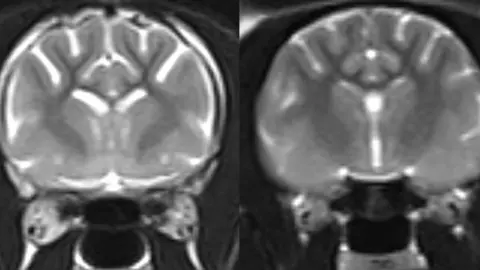

University of Edinburgh Black and white MRI scans of two cat brains. The one on the left has light areas which show brain loss, while the one on the right from a normal cat does not have the same light areas.University of Edinburgh